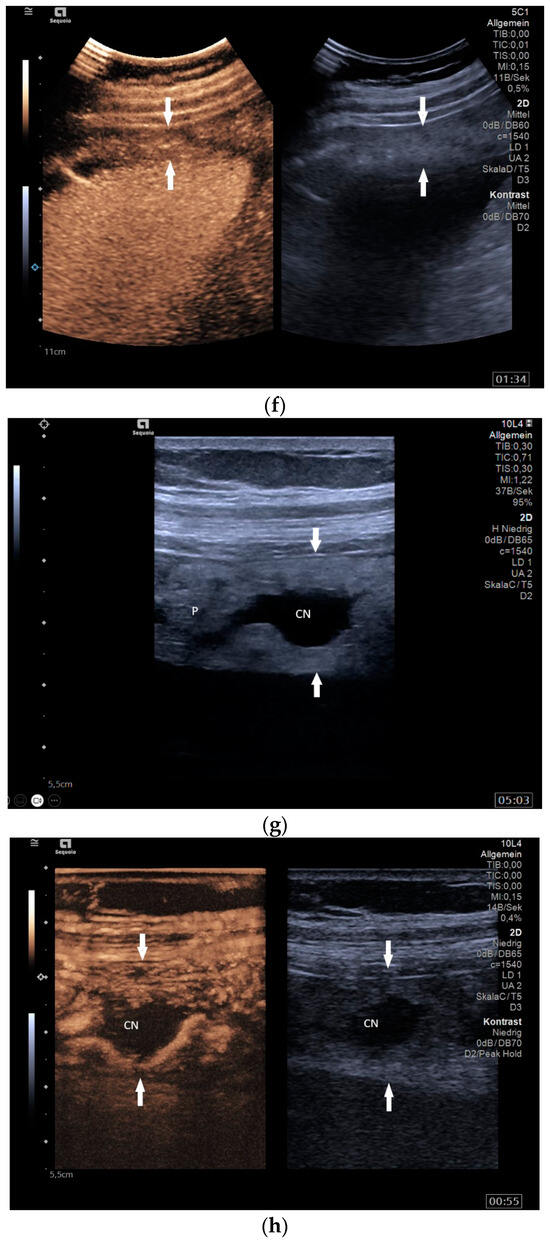

13.2. Adnexa, Fallopian Tubes, Uterus

Signs of tuberculosis in abdominal or vaginal ultrasounds in the female genital area are ovarian cyst, tubo-ovarian mass, hydrosalpinx, pyosalpinx, adhesion, adnexal fixation, thin endometrium, endometrial fluid, endometrial calcification, endometrial synechiae (Asherman’s syndrome), cornual synechiae, disturbed endometrial vascularity, ascites in the small pelvis, and peritoneal or omental thickening [122]. In a study with 175 infertile patients, ovarian cysts (23.4%) and tubo-ovarian masses (15.4%) were the most common manifestations [122] [Figure 8a–e].

Figure 8.

Tuberculosis of the uterus and adnexae. Female patients with tuberculosis in India. Pelvis with tubo-ovarian masses: Hypoechoic lesion in right adnexa (arrows) (a) and hypoechoic lesion in left adnexa and a small amount of free fluid (arrows) (b). Free fluid in the Douglas space (arrows) (c). Thickened right fallopian tube (RT FT) (arrows) (d); thickened left fallopian tube (LT FT) (arrows) (e).